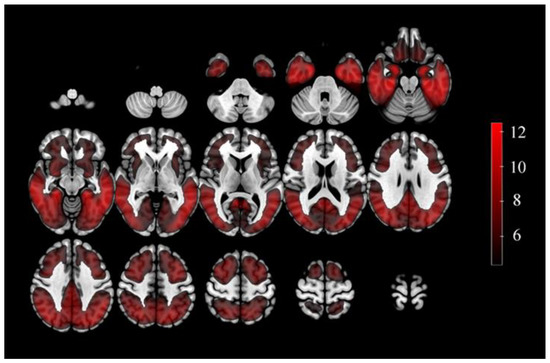

3.2. The Defined ROIs and Selected Features